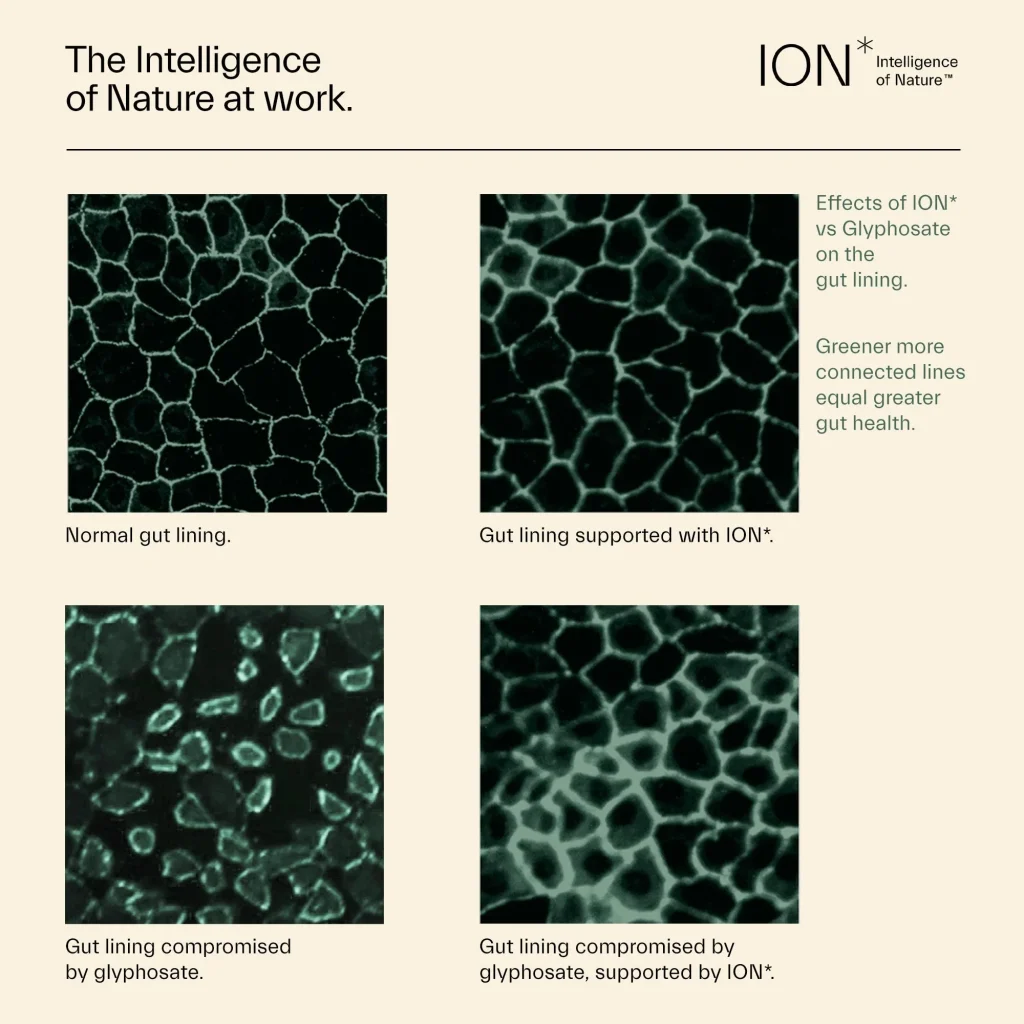

— ION* has been scientifically proven to strengthen the gut lining by sealing cell junctions, even in the presence of harmful toxins. This helps to combat intestinal permeability, thereby protecting the immune system, improving digestion, and supporting a healthy microbiome. Learn More

Proven to seal cells in the gut lining, ION* strengthens the terrain upon which your microbiome can diversify. Soil-derived fulvate helps tight junctions to keep toxins out while improving nutrient absorption and hydration. With tight junctions intact and a strong gut lining, ION* can help to combat indigestion, gas, and bloating.

Tighter cellular junctions mean a better terrain for your microbiome to diversify, a better environment to support good gut bacteria, and thereby an improved immune response. A stronger gut also means fewer toxins and inflammatory particles getting through that can spark an immune response.

Toxin Protection

ION* is proven to seal cells in the gut lining within minutes. With a strong gut lining, the body can work better to defend from toxins. Further, by acting as a carrier molecule, ION* works to move toxins out of the body, improving overall wellness.

ION* has been scientifically proven to strengthen the gut lining by sealing cell junctions, even in the presence of harmful toxins. This helps to combat intestinal permeability, thereby protecting the immune system, improving digestion, and supporting a healthy microbiome. Learn More

Drag the slider to see the difference between a strong, healthy gut lining (connected lines show tight junctions that are intact) and a gut lining compromised by toxins (gaps between cells indicate intestinal permeability).

ION*Gut + Microbiome supports the body’s natural production of beneficial enzymes through redox signaling (cellular communication). Those beneficial enzymes support the tight junctions (the seals between cells) in our gut lining – the barrier protecting us from toxic substances like glyphosate and gluten while allowing the entry of beneficial nutrients.

As demonstrated in our peer reviewed articles, toxins like glyphosate and gluten can degrade tight junctions in the epithelial layer of the gut lining. ION* Gut + Microbiome has been shown to promote the strengthening of this gut barrier, thereby bolstering the first line of defense against everyday exposure to toxins. With a strong gut lining, both digestion and immune function are improved. Further, by acting as a carrier molecule, ION* moves nutrients into the cells where they are needed the most